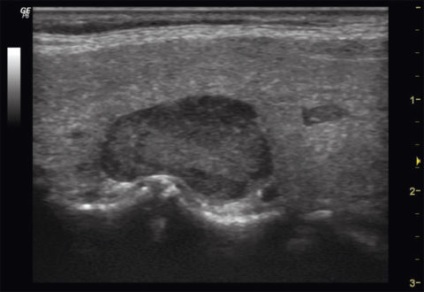

Mellékpajzsmirigy ultrahanggal

A normális állapotban, ezek az endokrin szervek ultrahang jelennek homogén hypoechoic ovális vagy lekerekített sima képződése szempontjából tiszta kontúrokkal, bármilyen mennyiségben legfeljebb 30 mm, amelyek vannak elhelyezve a felső és alsó pólusa a pajzsmirigy hátsó fal. Erezettség mellékpajzsmirigy a legtöbb esetben hiányzik.

Meghatározása egy ultrahangos belső áramlási csak akkor lehetséges, növeli a test mérete (32% az esetek másodlagos paraméterek 21H10 milliméter).

Hypoechogenicity mirigy csökken, a szerkezet inhomogén

Struck a személyazonosság vasból, heterogén szerkezetű, és bizonyos esetekben multilobular